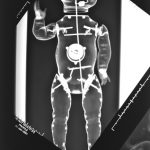

Distanced from the actual procedures (at the time) I was able to study these images for what they were. The half-familiar and recognizable bony structures, barium meal enemas, brain and body scans which became mingled with my X-rays of exotic flowers, fruit and vegetables (dipped in barium meal) plus dolls limbs and heads.

Similarities were seen between a pepper and a text book heart, a bundle of parsley and cerebral blood vessels. Dislocated dolls heads and limbs became floating body parts.